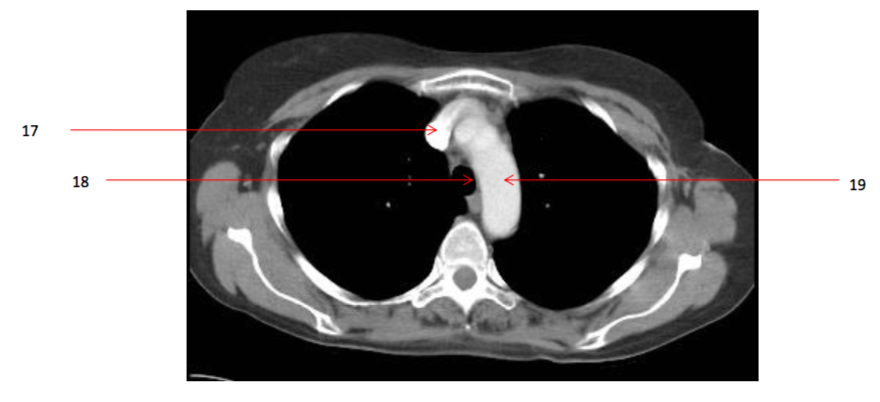

Number 19?

Arch of aorta

Number 17?

SVC

Number 18?

trachea